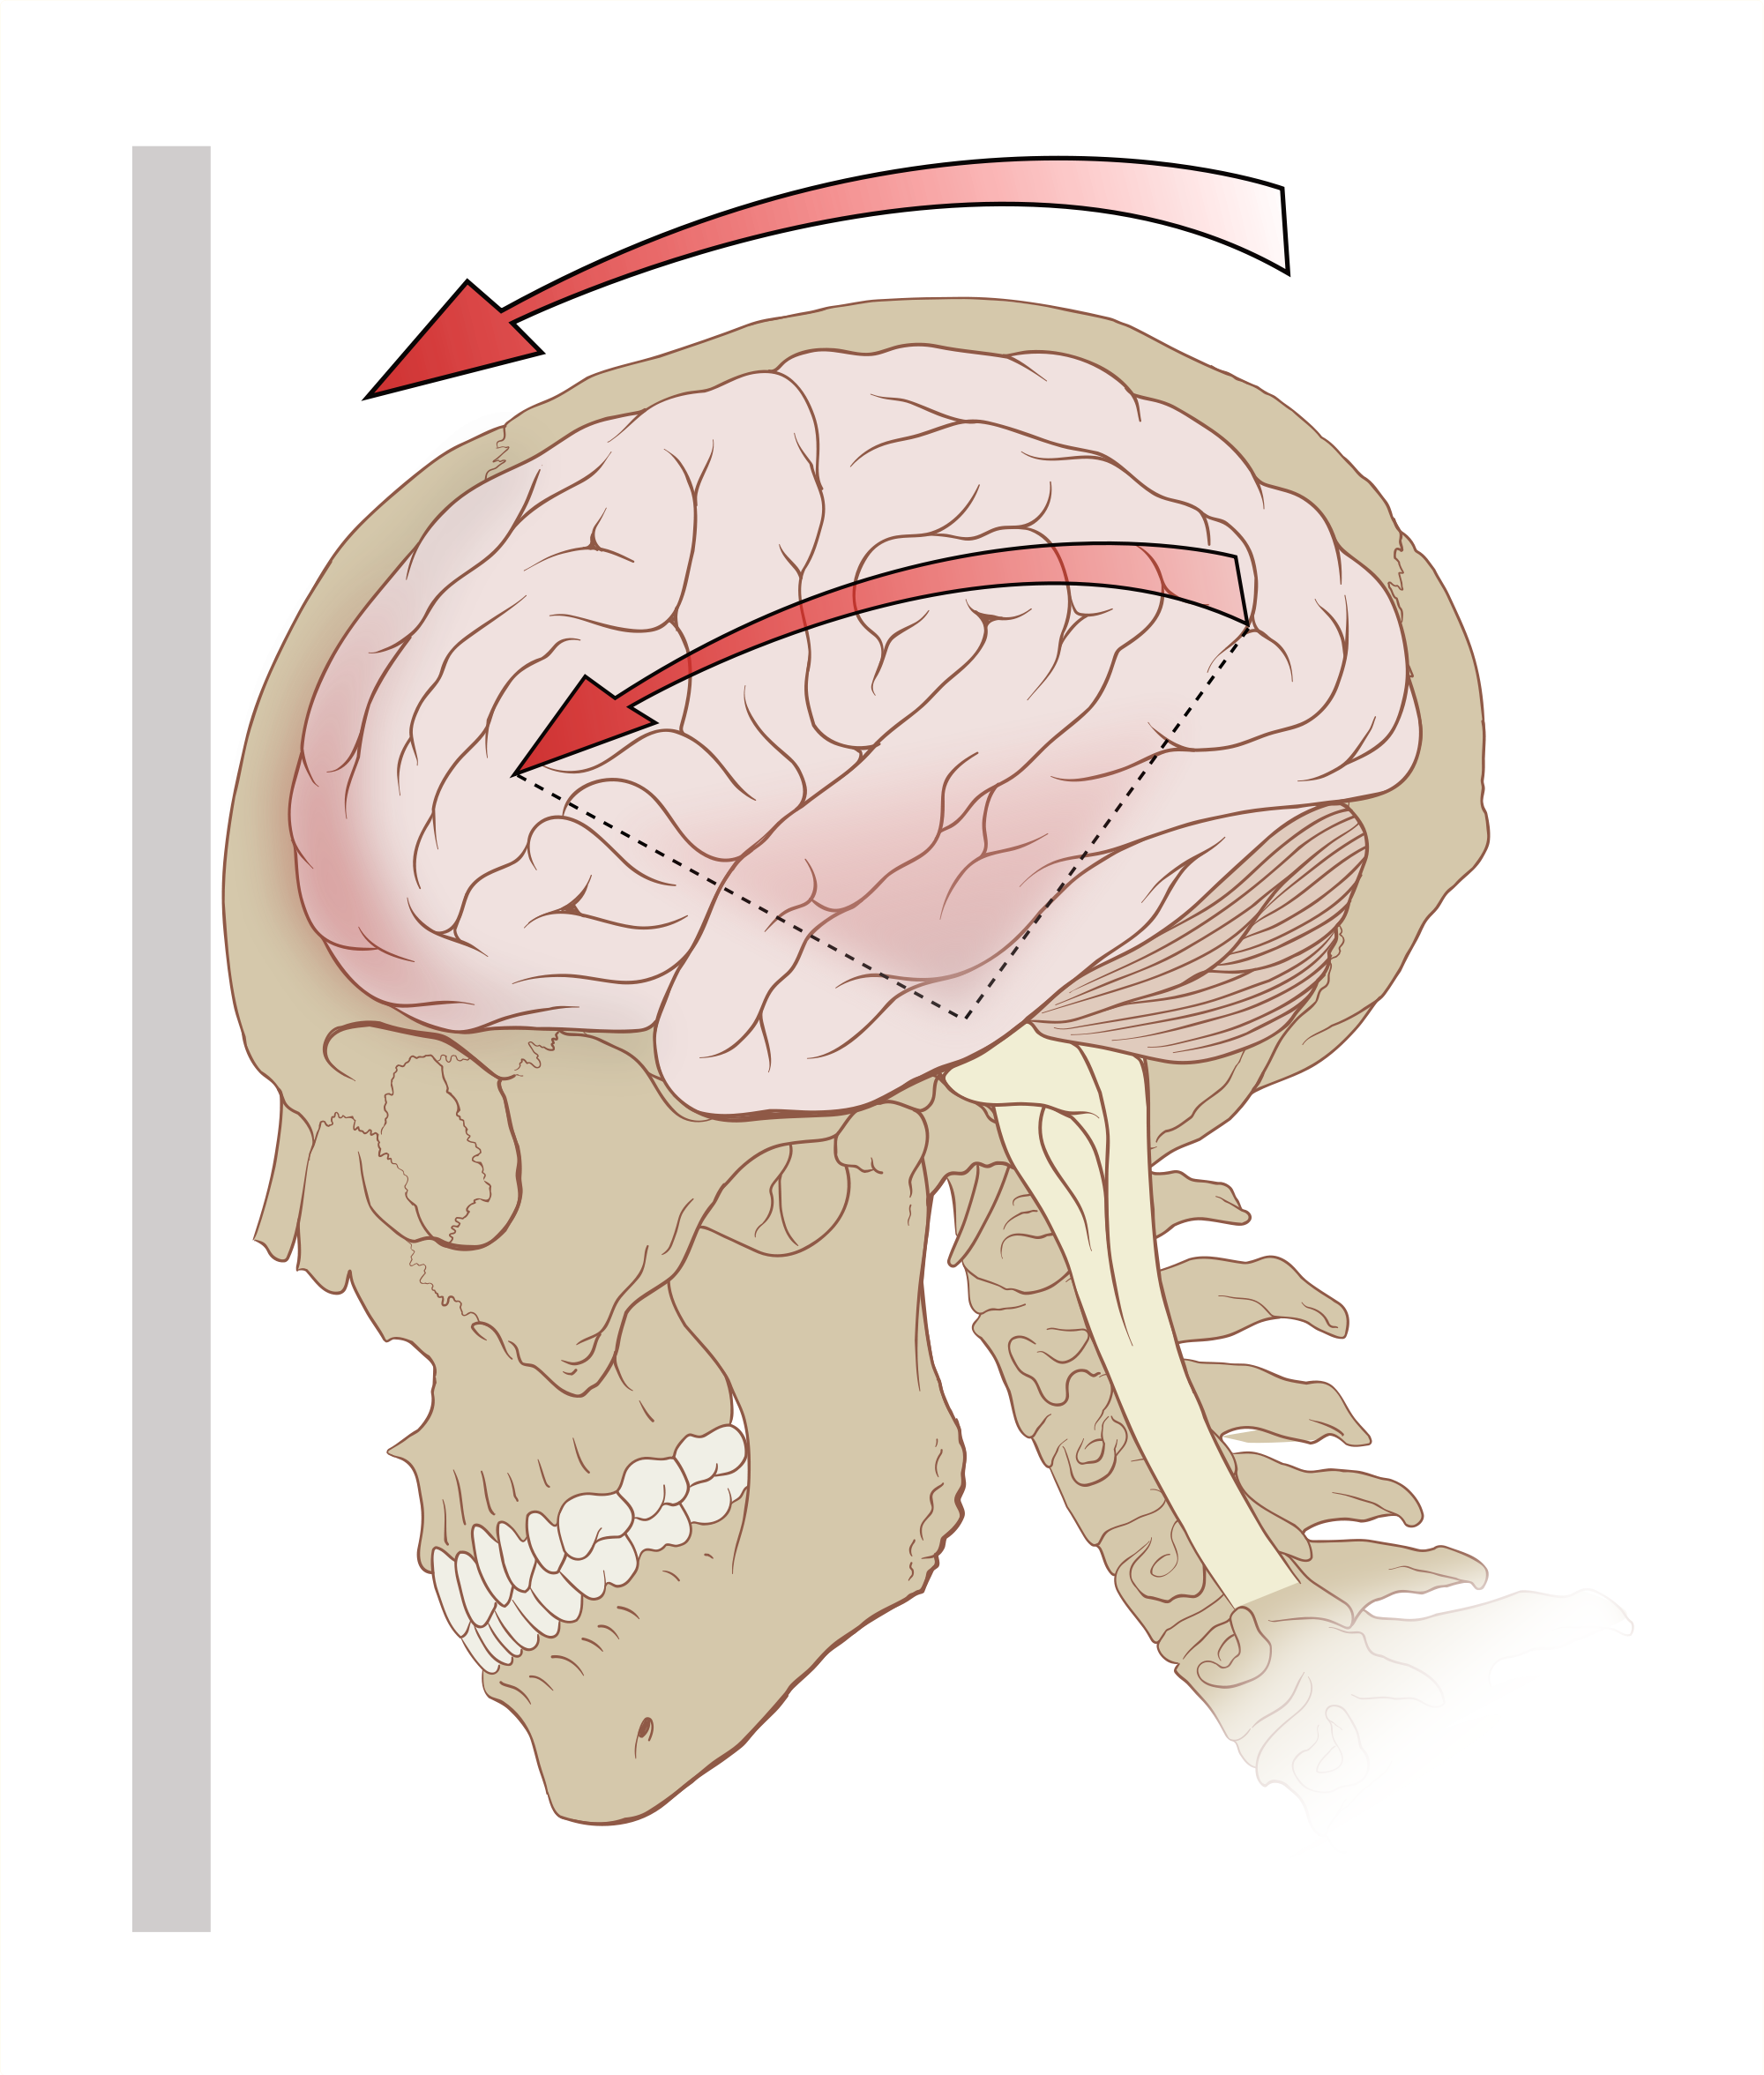

Contributor: Aaron Lessen MD Educational Pearls: Recent prospective randomized clinical trial assessed optimal head-of-bed positioning in patients with LVO 0º vs. 30º elevation Objective was to determine superiority of the two angles in stability prior to thrombectomy for LVO patients 45 patients randomized to the group with 0° head positioning and 47 patients randomized to the group with 30° head positioning Patients in the 30º group experienced worsening of NIHSS by 2 points or more Patients with head position at 0° showed score stability Hazard ratio 34.40; 95% CI, 4.65-254.37; P All-cause death occurred in 2 patients in the 0° group, compared with 10 patients in the 30° group. Results suggest that 0º positioning of the head of the bed may be protective to maintain clinical stability in patients with LVO prior to thrombectomy References Alexandrov AW, Shearin AJ, Mandava P, et al. Optimal Head-of-Bed Positioning Before Thrombectomy in Large Vessel Occlusion Stroke: A Randomized Clinical Trial. JAMA Neurol. 2025;82(9):905-914. doi:10.1001/jamaneurol.2025.2253 Summarized & Edited by Jorge Chalit, OMS4 Donate: https://emergencymedicalminute.org/donate/